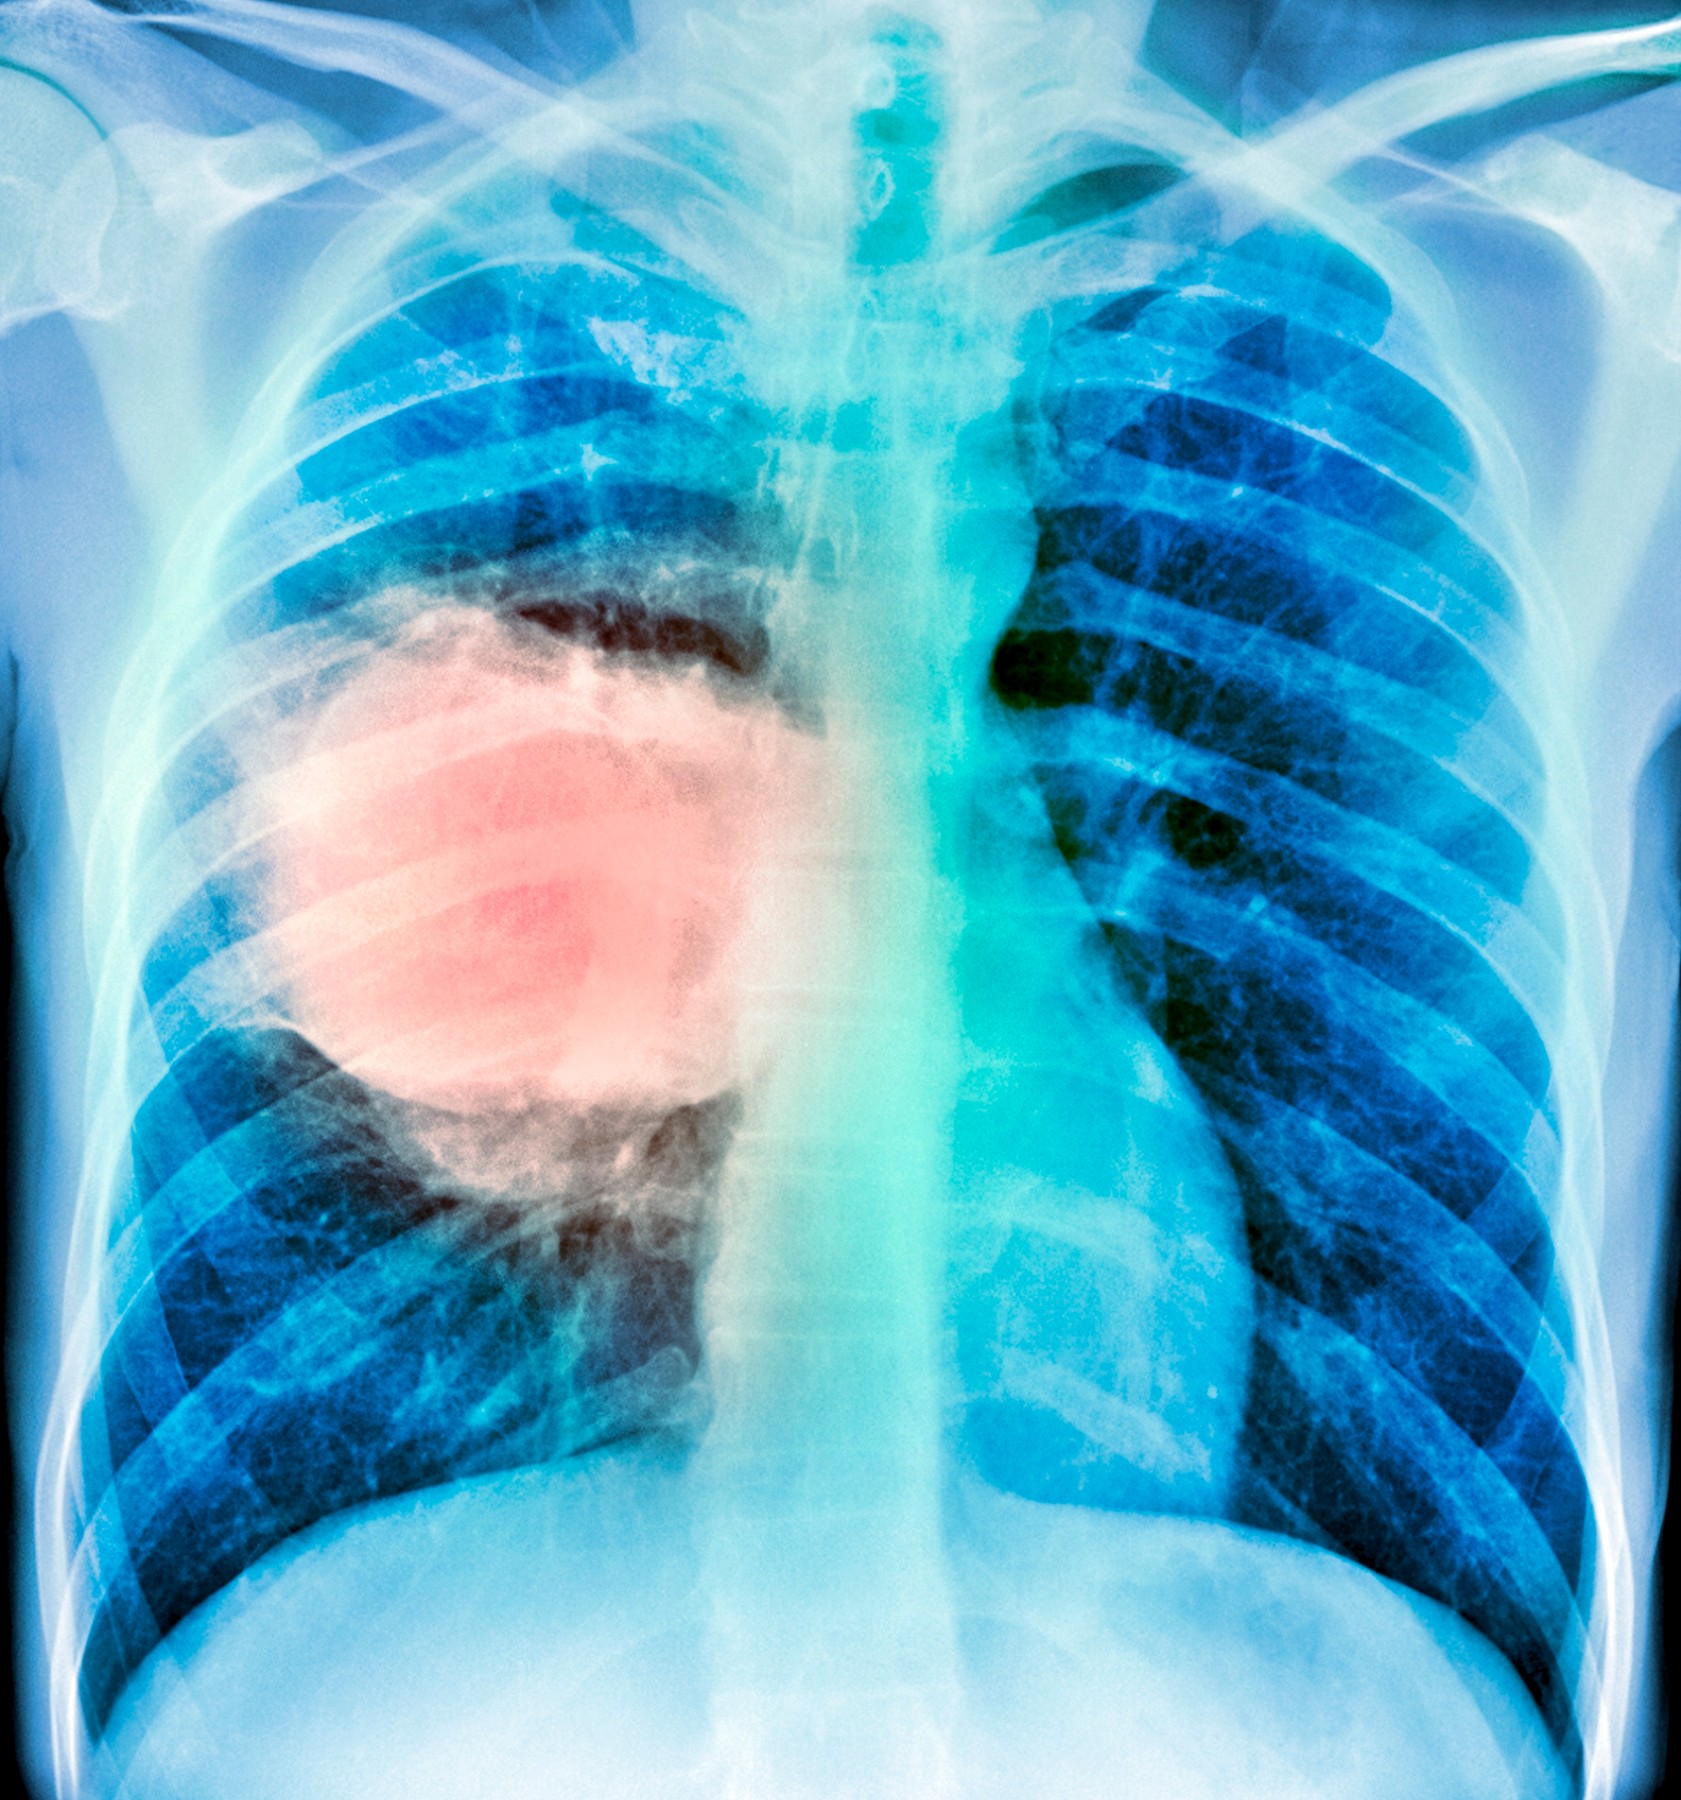

Zbog toga što se rijetko dijagnosticira na vrijeme, rak pluća može imati poguban ishod za bolesnika. Za dijagnozu se mogu koristiti CT, MR, PET snimanje, RTG i sken kostiju. Osim toga se može raditi citologija iskašljaja kako bi se potvrdilo postojanje malignih stanica te bronhoskopija kojom se ispituju dišni putevi.